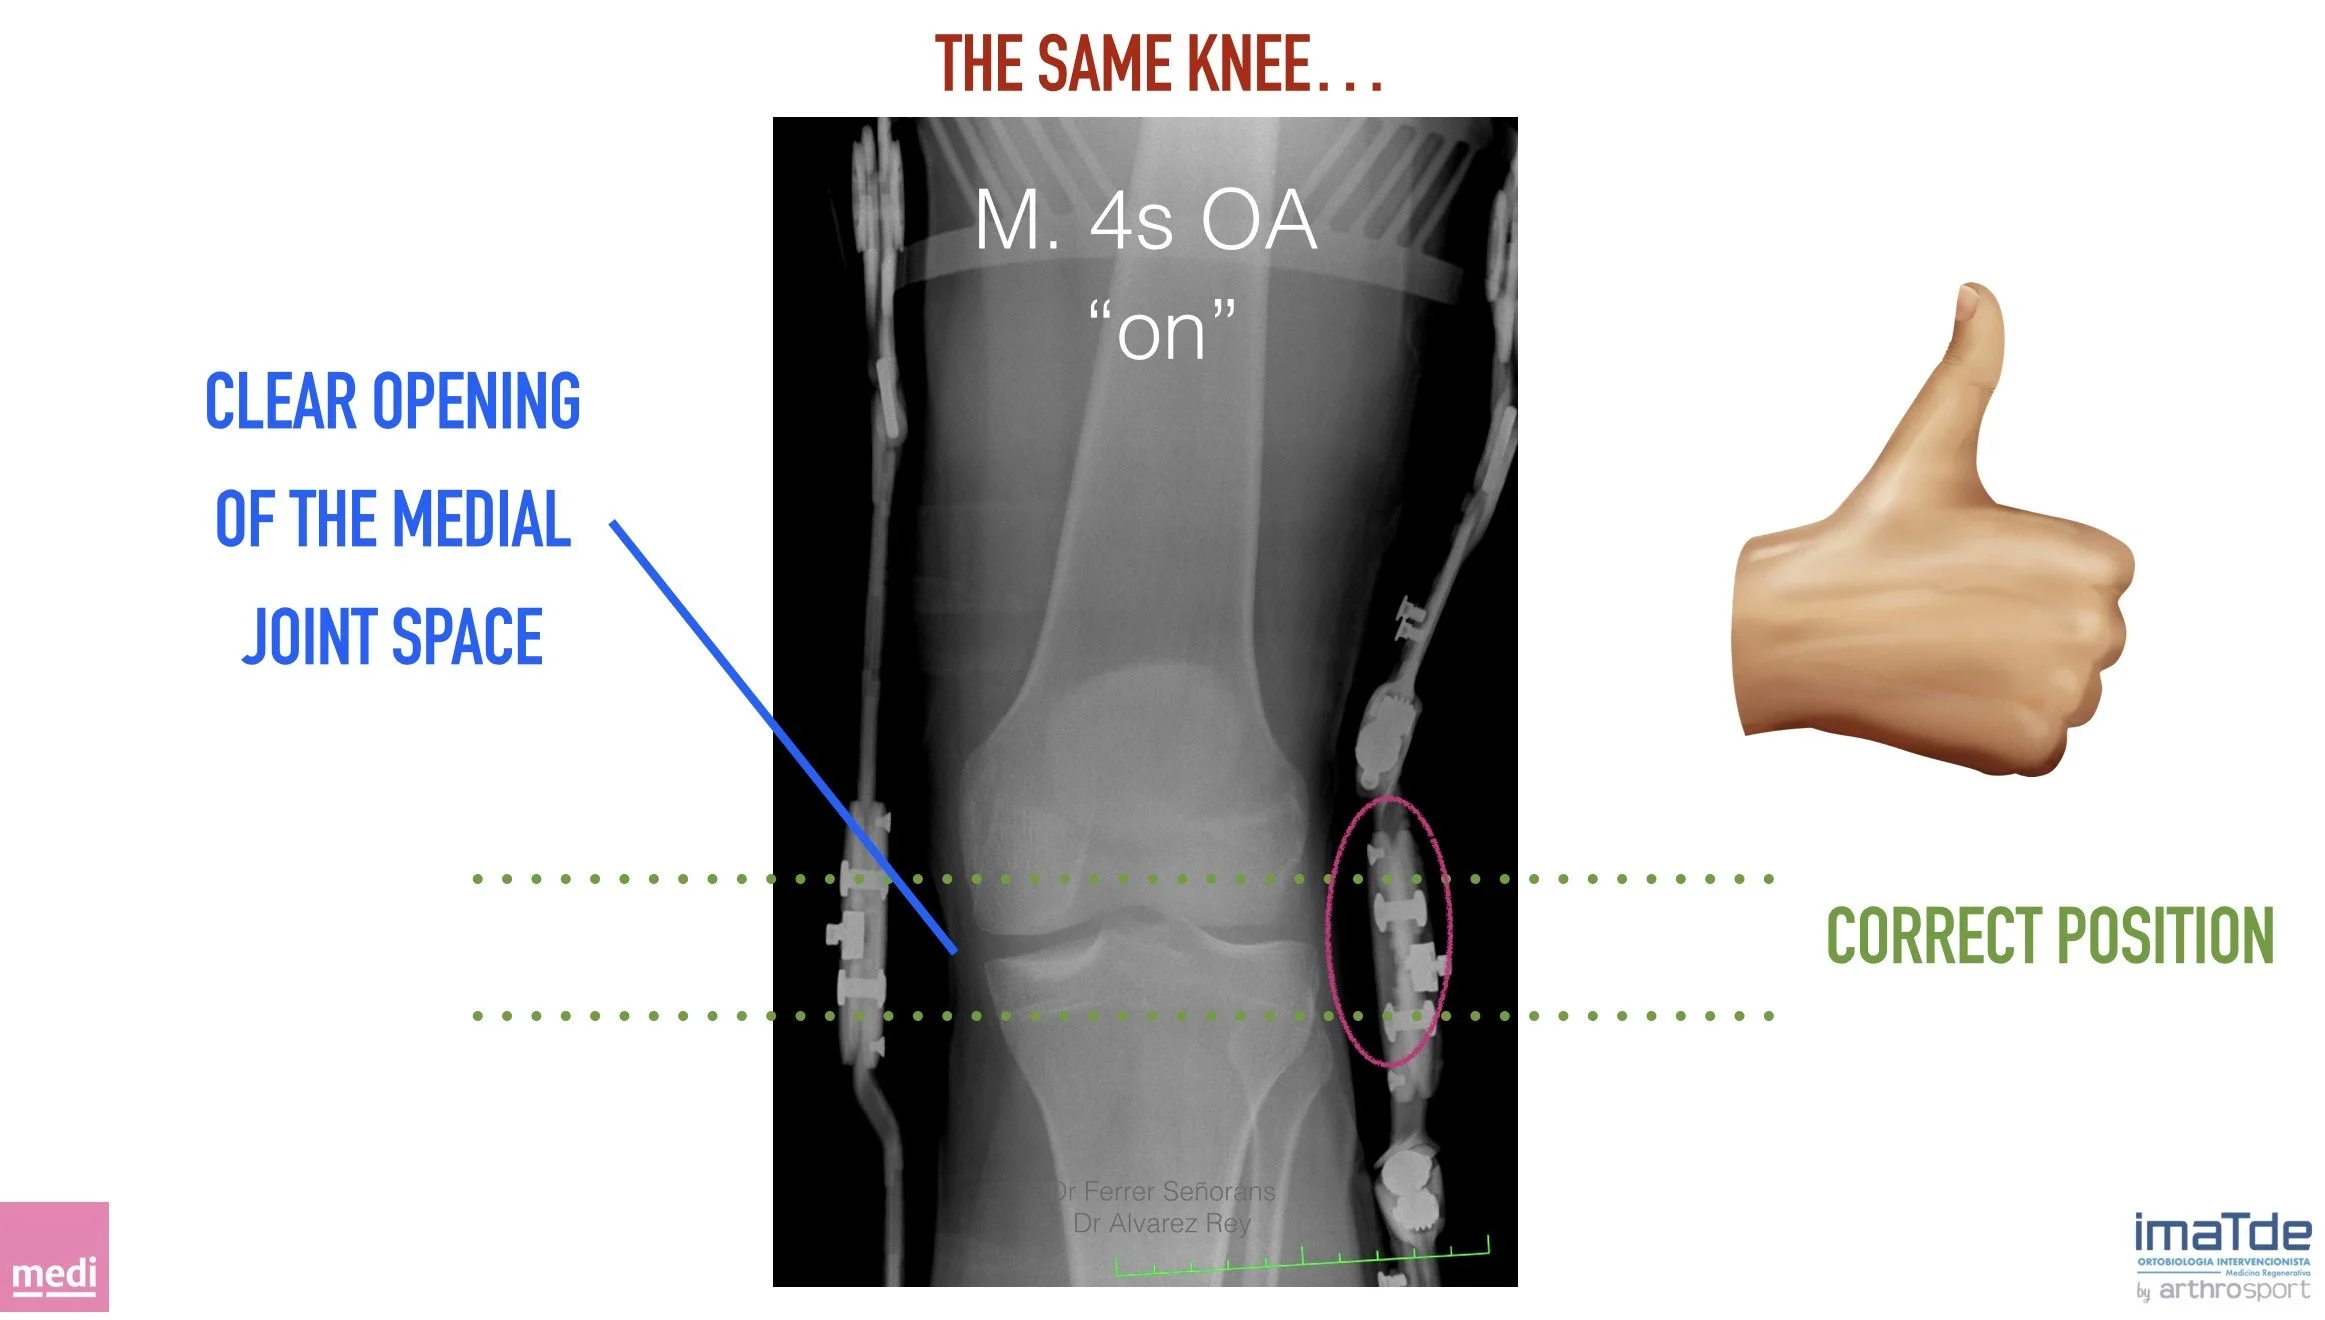

La órtesis M.4s OA permite reducir la presión sobre la zona afectada, descargando el compartimento dañado y favoreciendo la recuperación del hueso subcondral. Este soporte mecánico controlado, aplicado tras procedimientos regenerativos como la subcondroplastia biológica con PRP autólogo, ayuda a disminuir el dolor, mejorar la movilidad y retrasar la necesidad de una prótesis de rodilla en muchos pacientes.